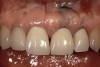

Rule 3: If a sulcus greater than 2 mm is found on the facial, evaluate the teeth esthetically to see if a gingivectomy could be performed to lengthen the teeth and create a 1.5-mm sulcus. Then, treat using Rule 1 (Figure 6, Figure 7, Figure 8, Figure 9, Figure 10 and Figure 11).

Figure 6  This 78-year-old female presented with maxillary anterior restorations placed 6 months earlier. She is unhappy with the fact that the margins are exposed and the tissue has receded following placement.

Figure 6

Figure 7   Sulcus depth from the existing attachment to the level of the existing margin is slightly greater than 3 mm. This is a patient who had an altered eruption pattern and a sulcus at the time these restorations were placed of over 3 mm.

Figure 7

Figure 8  Sounding to bone reveals a 3.5-mm distance, even following the recession.

Figure 8

Figure 9  The decision was made to perform a gingivectomy, leaving a 1-mm sulcus, then prepare the teeth 0.5 mm subgingivally on the same day.

Figure 9

Figure 10  Note that 4 to 6 weeks following the gingivectomy and re-preparation, the tissue is rebounding coronally over the margins of the temporary restorations.

Figure 10

Figure 11  This is a 4-year recall photograph following placement of the final restorations.

Figure 11